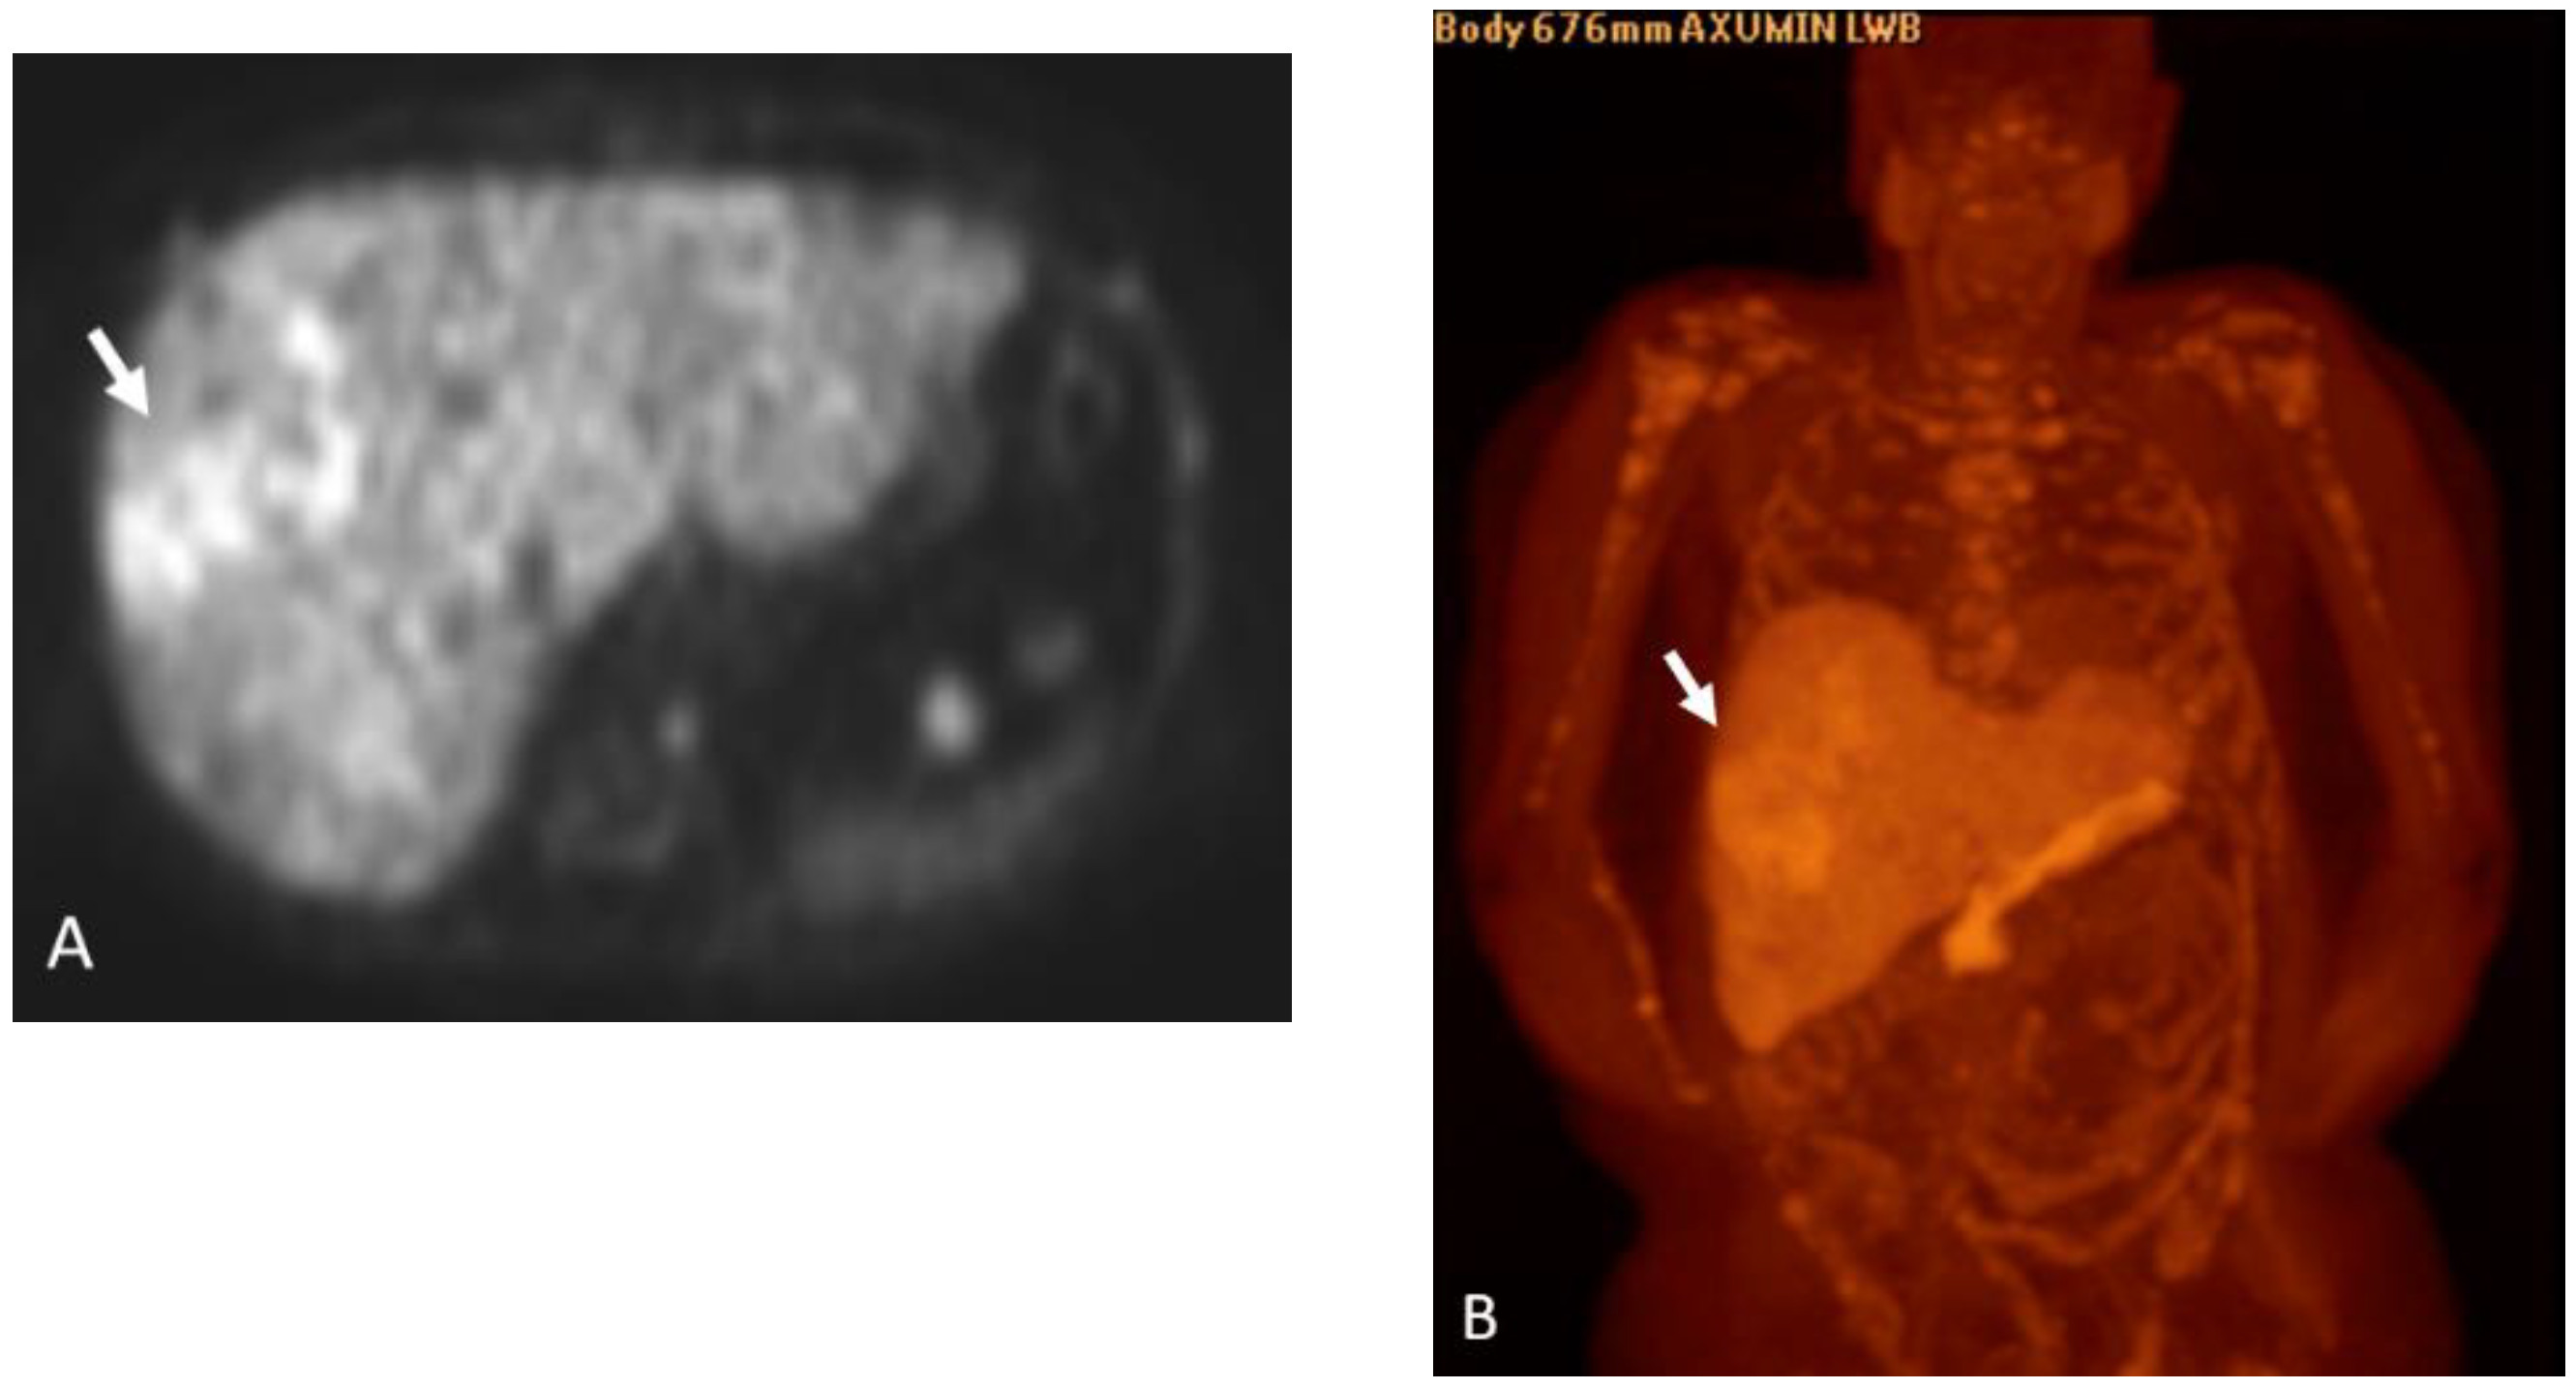

Detection of Loco-Regional Disease and Distant Metastases

1.9.2. PSMA PET

Detection of Loco-Regional Disease and Distant Metastases